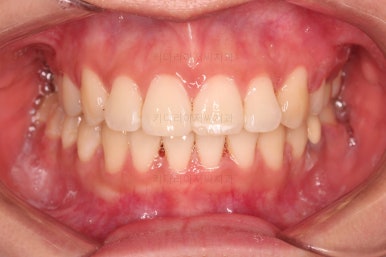

4. 마무리

틈이 다 없어졌고, 교합도 양호합니다.

무엇보다 임플란트 없이 결손부위가 깔끔하게 채워졌고요.

매우 다행으로 사랑니도 다 있었기 때문에 마치 큰 어금니가 다 있는 것과 같은 상황이 되었습니다.

역설적이게도 손상된 큰 어금니가 없었던 부위는 작은 어금니를 발치함으로 인해 오히려 치아 갯수가 모자라 보이는 상황까지 왔네요.(어금니가 결손된 부분이 더 자연스럽게 보이는 상황)

전후 비교 해볼게요.

입안의 모습은 더할나위 없이 잘 개선되었고요.

상하좌우 이 뽑은 위치와 크기가 달라 이정도 중앙선은 매우 잘 맞는 상황인거고요.